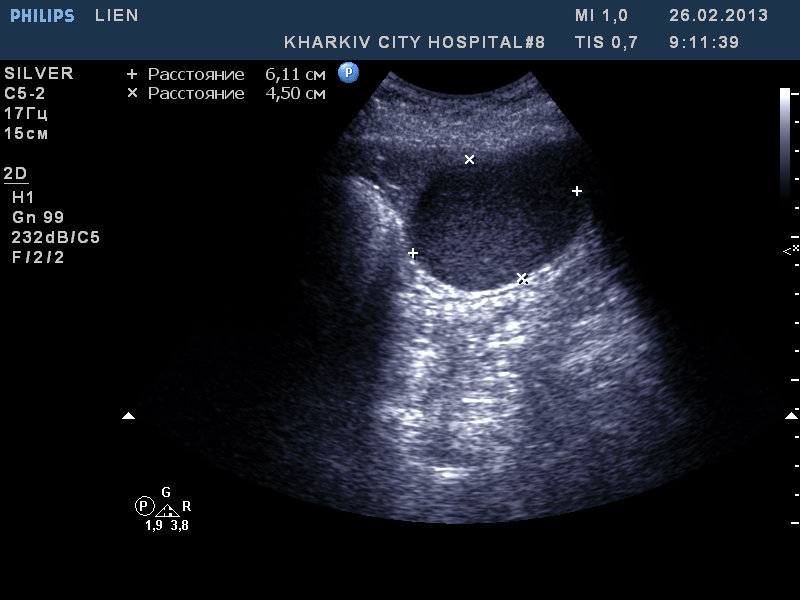

Re: образование селезенки

"Это становится интересным" © робот Вертер.

Рекомендовал КТ. Попробую узнать результат

Сегодня задренировал, содержимое - см. фото

Цитология: белковый преципитат, большое количество эритроцитов, лейкоцитов 5-8 в поле зрения.

Таким образом, видимо, в нашем случае это посттравматическая киста.

Дренаж удален на 4-й день, через трое суток при контрольном УЗИ - киста прежних размеров.